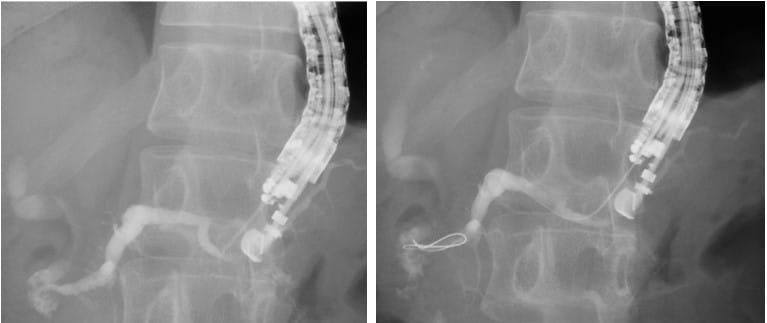

Esophageal Varices (Varicosities): Causes, Warning Signs & Treatment in Karachi Liver Health

Swollen veins in the food pipe (esophageal varices) can burst and cause life-threatening bleeding. Learn the causes, early warning signs, and treatment options available in Karachi.